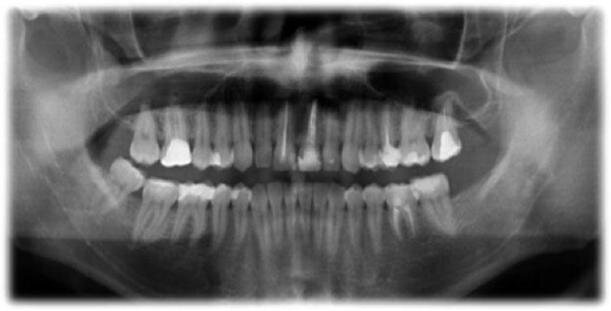

Kontrolę radiograficzną oraz weryfikację kliniczną przeprowadzono po 6 miesiącach (Ryc. 6), 1 roku (Ryc. 7), 2 latach (Ryc. 8) i 3 latach (Ryc. 9 i 10). W okresie prowadzonej obserwacji ząb pozostał całkowicie bezobjawowy, zaobserwowano jednocześnie gojenie tkanek okołowierzchołkowych.

Do często podawanych następstw przeszczepu zębów zalicza się ankylozę i resorpcję korzeni.43,44 W opisywanym przypadku klinicznym resorpcję wierzchołkową korzenia dystalnego można powiązać z przerwaniem unaczynienia oraz przewlekłym stanem AP (Ryc. 5).3,8,45